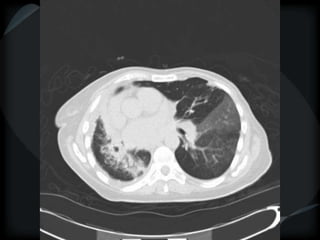

RETICULAR PATTERN - UIP

 peripheral reticular lines / inter and intralobular septae

 honeycomb

 Traction bronchiectasis

 None or minimal ground glass

 Gradient increasing from apex to base

 Skip areas

 Chronic HP = upper and midzones

Chronic HP

Asbestosis